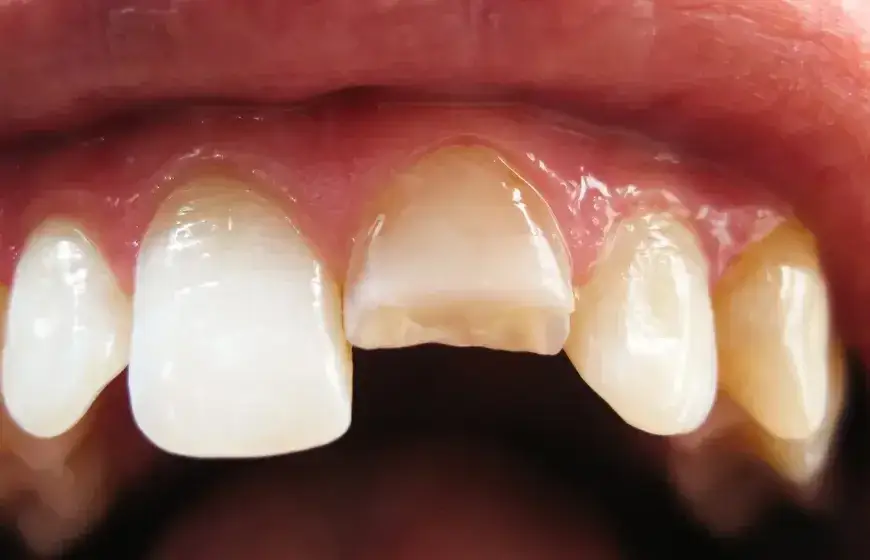

Pęknięcie guzka i korony zęba: jakie są szanse na pełną odbudowę?

Pęknięcia obejmujące guzek lub część korony zęba dają zazwyczaj wysokie szanse na pełną odbudowę i zachowanie zęba. W zależności od rozległości uszkodzenia, możemy zastosować odbudowę kompozytową, nakład (onlay) lub pełną koronę protetyczną. Celem jest przywrócenie funkcji i estetyki zęba, a także jego wzmocnienie, aby zapobiec dalszym pęknięciom. To jedne z tych przypadków, w których szybka reakcja pacjenta i moja interwencja przynoszą najlepsze rezultaty.